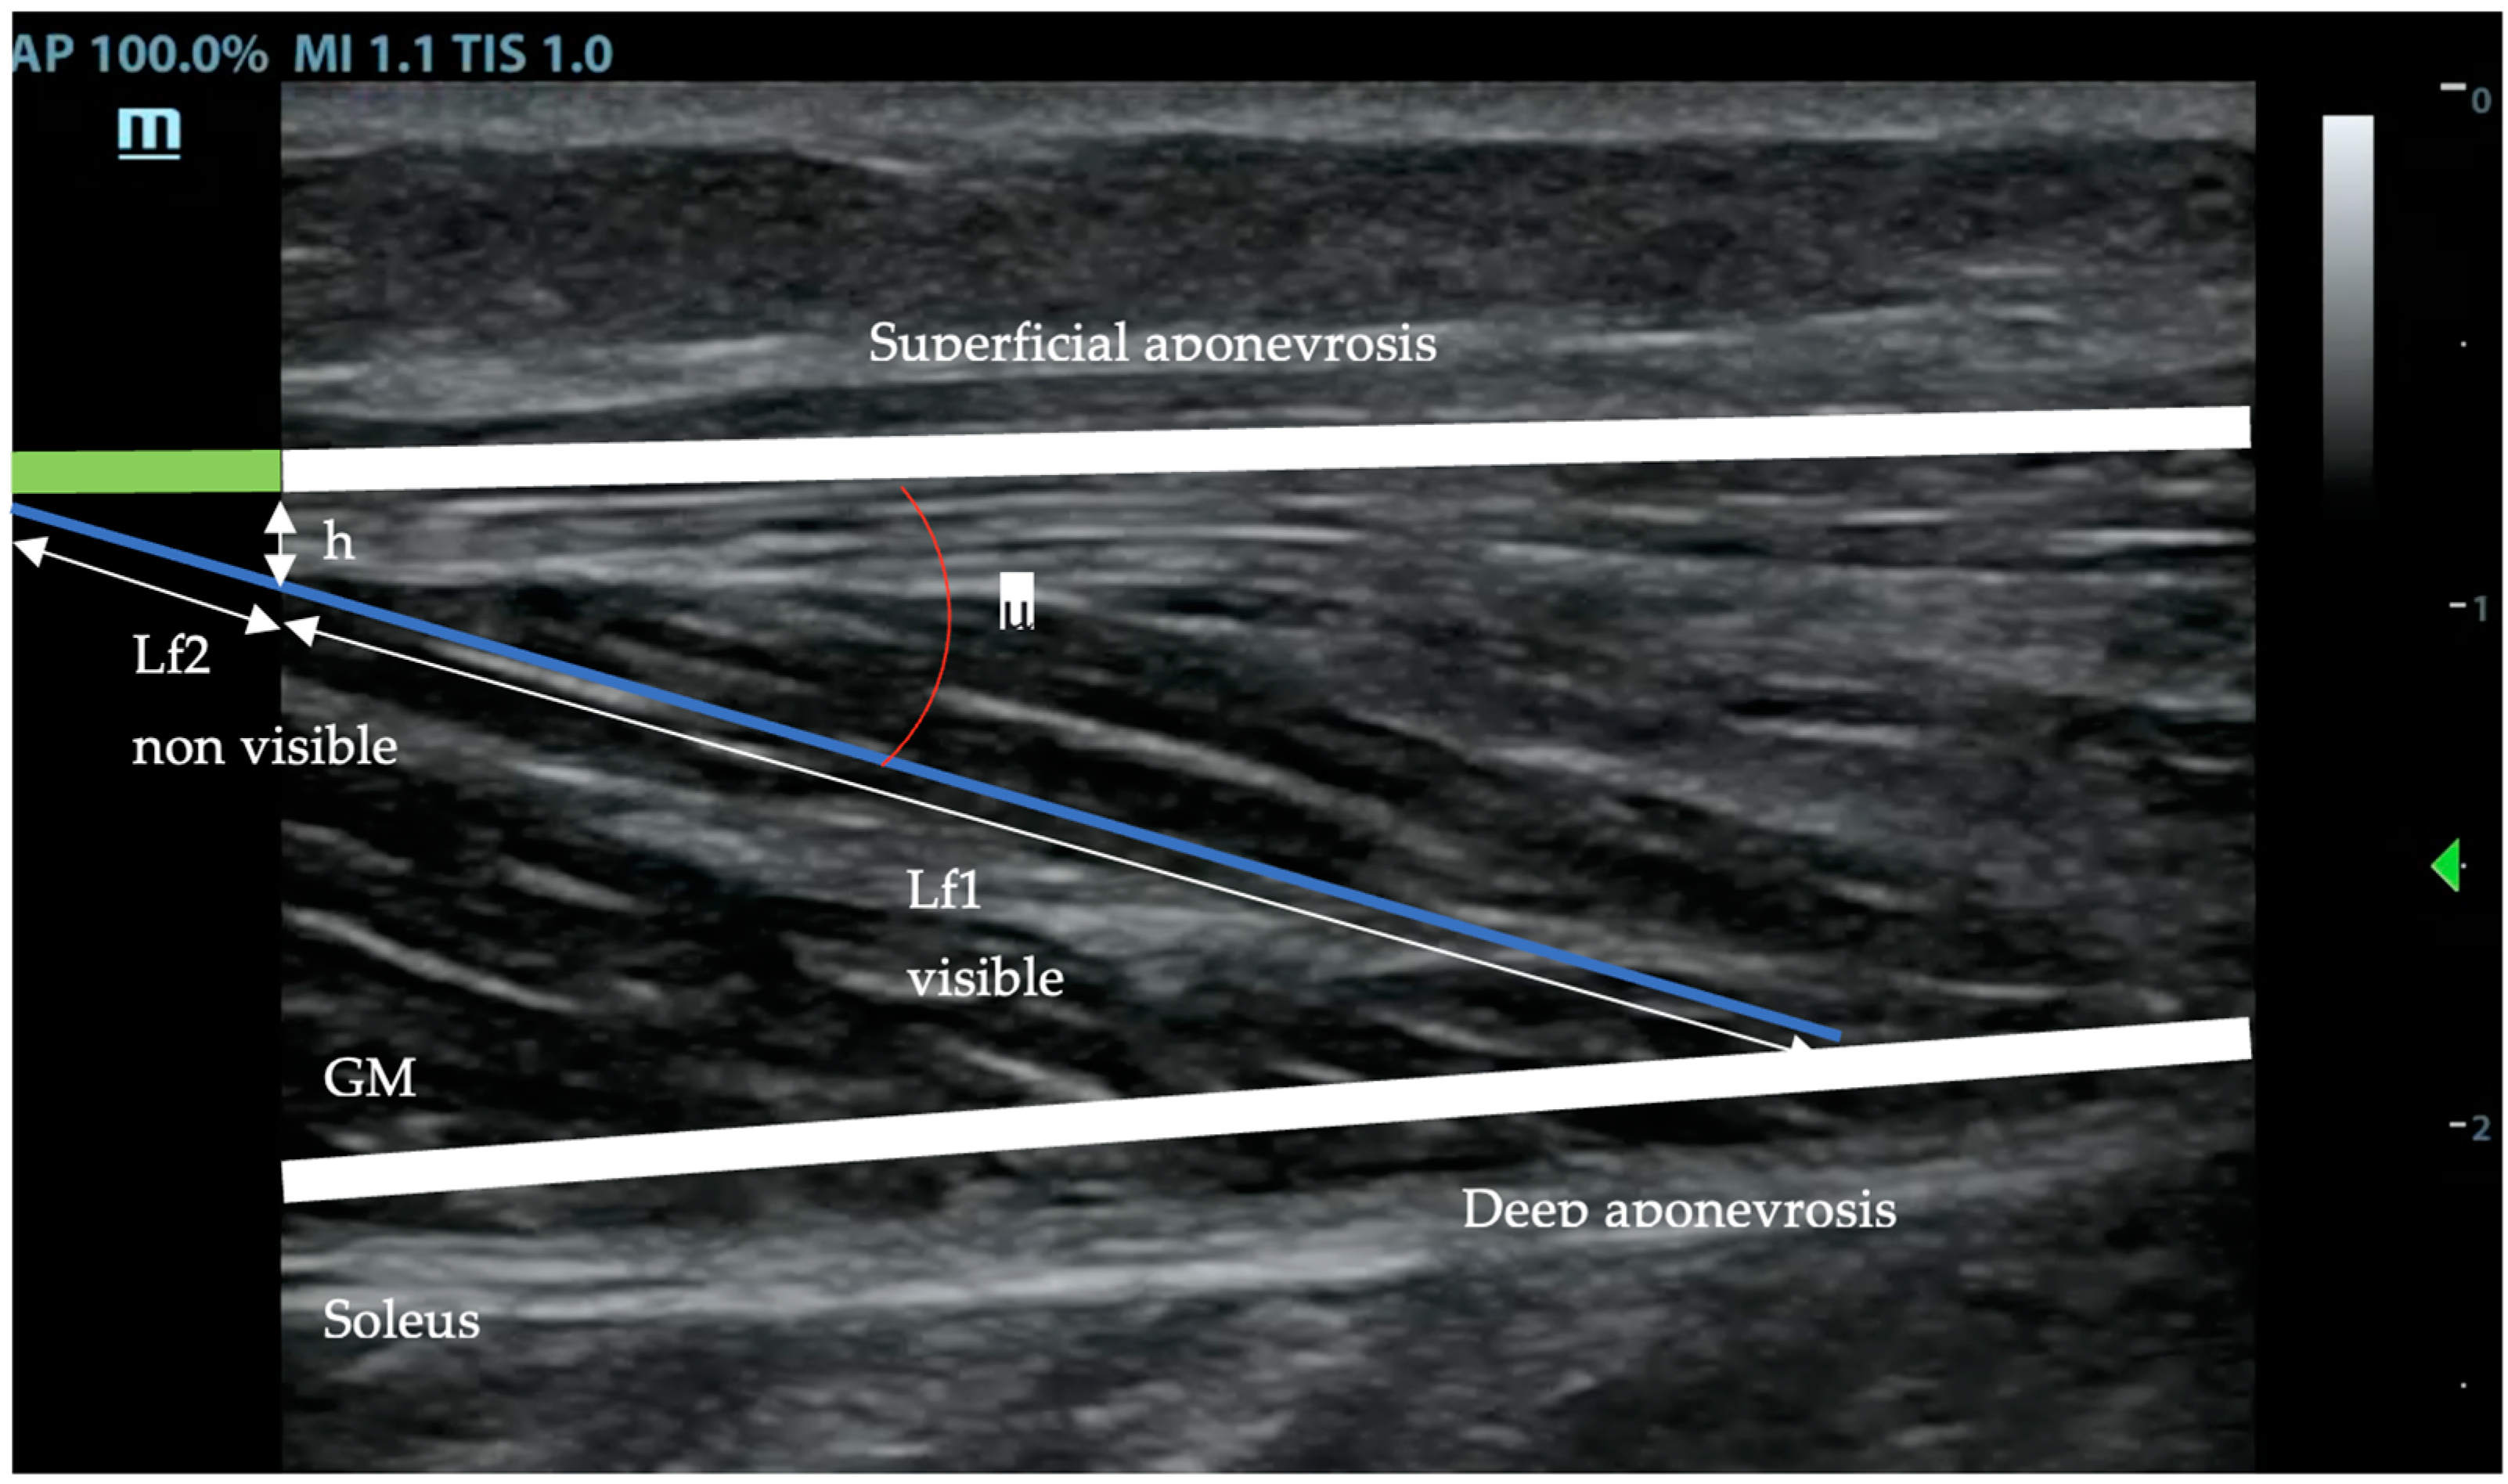

The fascicle length (Lf) was measured along the marked fibers’ bundle, from the superficial to the deep aponeurosis. When the end of the fascicle extended off the acquired ultrasound image, fascicle length (Lf) was estimated using trigonometry (total Lf = lf 1 measured + lf 2 estimated = lf 1 + (h/sin μ)) by assuming a linear continuation of the fascicles (Figure 2) [18,40].

Figure 2. Ultrasound image showing the measures taken to fill in the formula for the fascicule total length: total (Lf) = lf1 + lf2 = lf1 + (h/sin μ). This approach is necessary since direct full measurement of fascicule length is out of the probe vision.